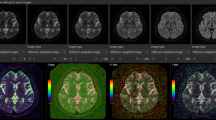

Acute MRI was performed after the ultrasound, within 1 h after the dive. Before the MRI acquisition, the rats were anaesthetized and a 25 Gauge neoflon was inserted in the tail vein. After a gradient echo, fast low angle shot (FLASH) pilot scan (acquisition time 1 min), a series of T2-weighted images were obtained to visualise anatomical changes and oedema using a turbo spin echo (rapid acquisition with relaxation enhancement, RARE) sequence with RARE-factor = 4, effective echo time (TE) = 25/50/75 ms, repetition time (TR) = 4,000 ms, 3 averages, acquisition time 7 min 12 s. Diffusion weighted images were obtained using an echo planar imaging sequence with 3 directions and 6 b-values (100/200/400/600/800/1,000 ms), TE = 53.47 ms, TR = 3,000 ms, 6 averages, acquisition time 8 min 24 s. For all of these scans, 17 coronal slices were acquired.

To visualise acute changes in brain perfusion and possible disruption of the BBB, dynamic contrast enhancement (DCE) studies were performed: at first, a T1-map was acquired using a RARE sequence with RARE-factor = 4, TE = 7.1 ms, TR = 341/562/845/1,243/1,913/5,000 ms, 1 average and acquisition time 7 min 55 s. This was followed by a pre-contrast T1-weighted image (RARE): TE = 7.0 ms, TR = 350 ms, 8 averages and acquisition time 1 min 41 s. Acquisition matrix (MTX) was 256 × 144 zero-filled to 256 × 192 giving an isotropic in-plane resolution of 156 × 156 μm2. Thereafter, a time-series of T1-weighted images was acquired (RARE-factor = 4, TE = 7.0, TR = 300 ms, MTX 128 × 72, zero-filled to 128 × 96, 1 average). With each image taking 5.4 s to acquire, 200 images were acquired over 18 min. After 60 s of acquisition, a dose of 0.3 mmol/kg 0.25 M gadolinium-based contrast agent (Omniscan, GE Healthcare, United Kingdom) (total volume ~0.36 ml) was injected intravenously through the neoflon over a period of 5 s. Finally, a post-contrast T1-weighted image was acquired with the same parameters as the pre-contrast T1-weighted scan. For all acquisitions, the field of view (FOV) was 40 × 30 mm and 7 slices á 1 mm was acquired.

On both 7 and 14 days after the decompression, diffusion tensor imaging (DTI) was performed to evaluate specific white matter injury and to look for changes in white matter. The DTI was acquired with an Echo planar imaging sequence using 30 directions and b = 1,000 ms, 5 images with b = 0 ms: FOV = 40 × 40 mm, MTX = 172 × 172 giving a resolution of 233 × 233 μm2. On day 7, TE = 37.5, TR = 3,000 ms, 17 slices á 1 mm were acquired with two averages giving an acquisition time of 14 min. On day 14 TE = 37.5, TR = 5,000 ms, 33 slices at 0.5 mm were acquired with six averages giving an acquisition time of 1 h 10 min.

MR image analysis

In-house developed software (MATLAB ver. R2010a, Math Works Inc, Natick MA, USA) was used to calculate apparent diffusion coefficient (ADC) maps by fitting a mono-exponential model to the signal intensity of the images with different b-values, while T2-maps were calculated by fitting a mono-exponential model to the signal intensity of the images with different TE-values. The same software was also used to calculate DCE parameters using the average signal intensities within the region of interest specified below. The following DCE parameters were calculated based on the T1-weighted image series acquired during and after gadolinium-based contrast injection: relative signal intensity (RSI) 1.5 min after contrast injection, RSI 1.5min , area under the curve (AUC) during the five first min after contrast injection, AUC 5min and time to peak signal (TTP).

All MR images were visually evaluated with respect to morphological changes and with abnormal signal areas. In addition, Medical Image Processing, Analysis and Visualization software (ver. 5.3.4, Centre for Information Technology (CIT), National Institutes of Health (NIH)) (McAuliffe et al. 2001) were used for regions of interest (ROI) analyses of the image data. ROIs in the frontal, parietal and occipital cortex, hippocampus, putamen, thalamus and brain stem at the level of pons were drawn in the T2-maps (Fig. 1) and copied to the ADC-maps and T1-weighted images to ensure the same placement of ROIs in all image sets. Average voxel values in each of these regions were calculated and compared between groups. The same ROIs were also used to calculate DCE parameters, as described above. For the T1-weighted images used for manganese-enhanced MRI 1 week after the dive, ROI were also drawn in muscle areas lateral to the brain on both sides. Using the average signal intensity from muscle, the mean relative contrast (RC) was calculated in all the other ROI using the formula:

DTI analyses were performed with the tools of the FMRIB software library (FSL ver. 4.1.4, Oxford Centre for Functional MRI of the Brain, UK; www.fmrib.ox.ac.uk/fsl). Images were pre-processed to reduce image artefacts due to motion and eddy current distortions by affine transformation and co-registration of the diffusion encoded images to the b 0 images. Single data sets with severe ghosting artefacts were excluded from further analyses (day 21: n = 6, day 42: n = 5). Brains segmented out using the Brain Extraction Tool before FDT ver2.0 (both part of FSL) was used to fit a voxel wise diffusion tensor model to the diffusion image data (Behrens et al. 2003). Maps for the fractional anisotropy (FA), mean (MD), radial (RD) and axial diffusivity were created for all animals for days 7 and 14 after decompression. ROI were drawn in the internal capsule, external capsule, hippocampal fimbria, body and splenium of corpus callosum on the FA-maps. Mean FA, MD, RD and axial diffusivity were calculated in each ROI in each animal.

Acute MRI findings

Decompressed rats had a different time-curve for the dynamic contrast-enhanced MR signal than controls, with higher RSI (P = 0.017), a tendency towards longer time to peak (P = 0.11) and a larger area under the curve for the whole brain (P = 0.099) (Fig. 2). Region of interest based analyses of the dynamic contrast-enhanced MRI (DCE MRI) data that showed differences between decompressed and control animals in frontal cortex and thalamus. Decompressed animals had higher mean RSI (P = 0.023, Table 1) and a tendency towards higher TTP and AUC in the frontal cortex than control animals (P = 0.076 and P = 0.068, respectively). In the thalamus, AUC was higher among decompressed animals (P = 0.033, Table 1) with a tendency towards higher RSI and TTP (P = 0.068 and P = 0.104, respectively). For all other areas, there were no significant differences between the two groups.

Interestingly, the variation in all three parameters (RSI, TTP and AUC) was higher among decompressed animals than controls. There were no specific areas with increased signal in the post-contrast image compared to the pre-contrast image. The ADC-maps and T2-maps did not show any focal changes indicating pathology in neither the decompressed nor the control animals. Measurements of ADC and T2 in several brain areas showed no differences between the groups (Tables 2 and 3).

MRI 1 and 2 weeks after decompression

The T2-maps showed no signal abnormalities or morphological changes 1 or 2 weeks after the decompression. Region of interest based measurements of T2 showed higher T2 in the brain stem among decompressed animals than controls after 1 and 2 weeks, with the same tendency seen in thalamus (Table 3). There was also a similar reduction in T2 in both groups from time 0 to week 1, with a slight increase to week 2 (Table 3) which was related to the administration of manganese on day 1 after decompression. Visual inspection of T1-weighted images after 1 week showed similar manganese-enhancement in both groups, and region based analysis of the images did not show any differences between groups in relative contrast 1 week after administration of MnCl2 (Table 4).

No specific white matter abnormalities were seen on DTI and parameters such as fractional anisotropy (FA) (Fig. 3), mean, axial and radial diffusivity were not different between groups in the measured white matter structures (Table 5).